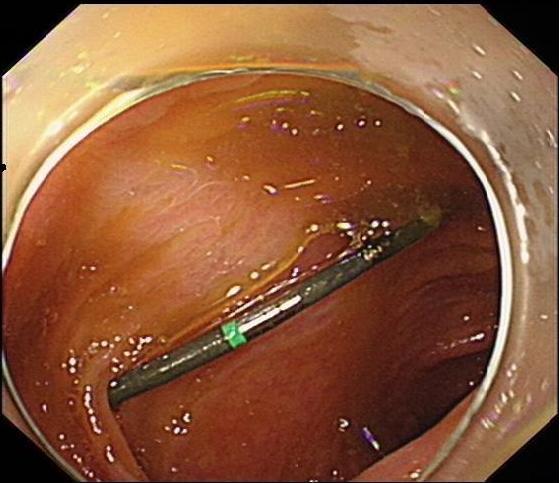

2.2 术前准备及术中配合根据无痛胃肠镜要求,对患者进行肠道准备及禁食禁饮宣教,护士加强患者心理支持,并做好仪器设备准备,如抢救车、除颤仪等。结肠镜前端置透明帽后循腔进镜,经直肠、乙状结肠、降结肠、横结肠时,见1个条形金属异物,长约3 cm(图 7),观察到一端已插入肠壁,首先选用异物钳将插入尖锐端金属轻轻拔出。为避免金属钻易脱落,强行取出异物容易造成肠道二次损伤,改用圈套器将尖锐端套住收紧后拉入透明帽内配合医生不断变换角度,调整方向,使异物方向和镜身尽量保持平行(图 8)缓慢通过各结肠弯曲部,顺利将异物取出(图 9)。整个内镜操作过程只用了15 min,无出血和穿孔等并发症发生。

| 图 8 圈套器将尖锐端套住收紧后拉入透明帽内,调整方向,使异物方向使镜身尽量保持平行,缓慢通过各结肠弯曲部 |

3 讨论结肠异物较上消化道异物、直肠异物少见,大多数为经口吞入异物,并随着肠蠕动进入至结肠。目前针对下消化道异物处理国内外暂无指南或专家共识,临床上基本按照上消化道异物处理策略开展。结肠异物的诊断主要依赖于腹部体格检查、病史采集、腹部CT/X线检查。其治疗主要根据患者的症状、异物的大小、性质及滞留位置决定[13]。吕颜智等[14]通过血清降钙素原对急性消化道出血部位进行预测,发现下消化道穿孔者血清降钙素原有较好的预测作用。可作为判断是否发生穿孔的指标之一。本例患者采用多学科联合协作,联合放射科、外科等制定诊疗和应急预案,选择最佳治疗方案,成功在内镜下取出迁移性结肠异物,无并发症的发生。护士在操作配合中需注意:(1)肠镜前端使用内镜专用透明帽,收住尖锐异物后要拉入透明帽内,与镜身保持平行(图 8),可防止异物尖端撕裂黏膜;(2)术中异物钳改用圈套器能更牢固收紧尖锐异物,防止退镜过程中因异物脱落或划伤黏膜造成二次损伤[15]。